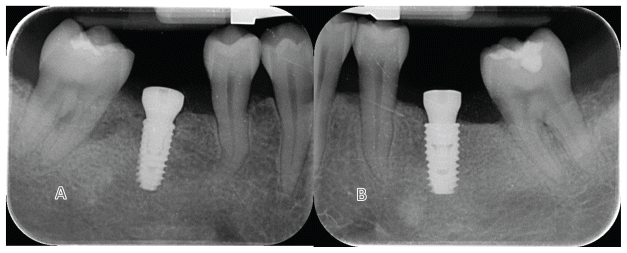

In the test group, Osstem KS BA implants (4.0 mm diameter, 15° internal taper connection, Osstem Implant) were placed. In the control group, Osstem TSIII BA implants (4.5 mm diameter, conventional 11° internal connection, Osstem Implant) were used (Figure 1). All patients underwent radiographic examination (periodical radiograph with paralleling technique) and professional oral hygiene treatment before surgery.

All surgeries were performed under local anesthesia with articaine hydrochloride and adrenaline 1:100,000 (Orabloc, Pierrel, Milan, Italy). After crestal incision and full-thickness flap elevation, implant sites were prepared either freehand or with the aid of a surgical guide. Manufacturer’s recommended protocols were followed (Osstem Implant). Bone quality was assessed subjectively. The first site was randomly assigned to receive either the KS (test) or TSIII (control) implants (Osstem Implant). Implants were placed at the crestal level or up to 2 mm subcrestally, based on anatomical conditions. Healing abutments were immediately connected if primary stability was ≥30–35 Ncm. On the contrary, cover screw would be place and second stage surgery planned. Flaps were closed with Vicryl 4.0 (or equivalent). Baseline periapical radiographs were taken with paralleling technique, for each study implant to prevent the risk of systematic error in performing periapical radiographs. Two to three months post-placement, either digital or conventional impressions were taken. Within one month, monolithic zirconia crowns bonded to titanium links were delivered after testing implant stability. Occlusal contacts were adjusted for light contact with the opposing dentition. Clinical photographs and radiographs were taken. Oral hygiene instructions were reinforced. Patients were enrolled in a maintenance program with six-month intervals. At each visit, professional oral hygiene sessions and clinical evaluations were performed, with particular attention to implant stability and occlusion. In addition, periapical radiographs were taken annually. According to the study protocol, patients were followed for research purposes for up to 5 years. Radiographs of both treatments are reported in figures 2–5. At each center, a single experienced clinician performed all surgical and prosthetic procedures, with optional assistance from a second clinician (e.g., a prosthodontist). All interventions and follow-ups were conducted at the respective sites using standardized materials and protocols to ensure consistency.

- Rate (expressed in mm) of peri-implant marginal bone level (MBL) changes were assessed on periapical radiographs took with the paralleling technique at implant placement, at initial loading, 6-month, 1,3 and 5 years after loading. In case of an unreadable radiograph, the radiograph has to be made again. Ideally digital radiographs should be taken, otherwise radiographs on conventional films will be scanned into TIFF format with a 600 dpi resolution, and stored in a personal computer. Peri-implant marginal bone levels were measured using the Scion Image (Scion Corporation, Frederick, MD, USA) software. The software was calibrated for every single image using the known distance of the first two consecutive threads. Measurements of the mesial and distal bone crest level adjacent to each implant were made to the nearest 0.01 mm. Reference points for the linear measurements were: the coronal margin of the implant collar and the most coronal point of bone-to-implant contact. Bone levels were measured at both mesial and distal sides and averaged. Bone levels were averaged at implant level and finally at group level.